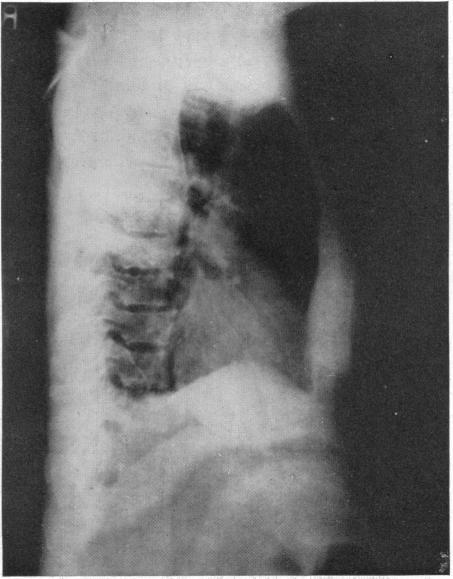

INTRATHORACIC DERMOIDS: WITH THE REPORT OF A CASE OF TOTAL EXTIRPATION AT ONE SITTING BY A NEW METHOD OF THORACOTOMY.

Ann Surg. 1928 Sep;88(3):607-32. doi: 10.1097/00000658-192809000-00030.